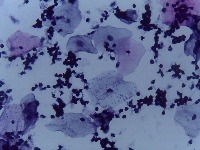

Medical Diagnostics: This model can be used in the healthcare industry to provide high-speed automated analysis of pathology slides, determining whether cells are normal or abnormal, and assisting in diagnosis of various diseases such as cancer.

Scientific Research: Researchers studying cell biology or genetics can use this AI model for their studies on cellular abnormalities and diseases. This can accelerate the onset of breakthroughs in medical science.

Pharmaceutical Applications: Pharmaceutical companies can use this model in drug discovery and development process. By identifying how different medications affect normal and abnormal cells, they can speed up and enhance their research.

Educational Tool: This AI model could serve as a rich educational tool in courses related to biology, medicine and health sciences, helping students to visualize and understand differences between normal and abnormal cells.

Personalized Medicine: This model can be used to analyze patients' cells to create personalized treatment plans. Understanding an individual's cellular structure could help healthcare professionals tailor treatments to the patient's specific needs.